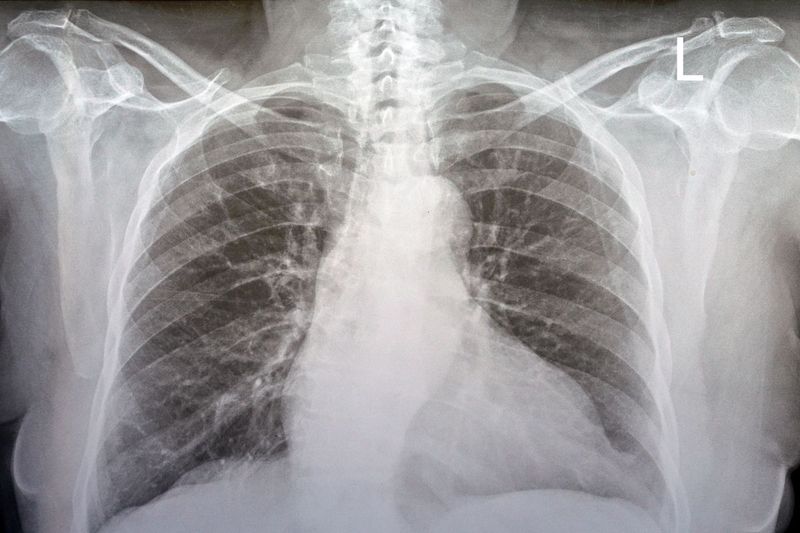

この問題は、北米放射線学会(RSNA)の査読付き学術誌『Radiology(ラジオロジー)』に掲載された最新の研究結果で明らかになった。研究では、6カ国・12施設の放射線科医17人に胸部X線(レントゲン)画像を見せて評価してもらった。用意した画像154枚のうち、半数は本物のレントゲン写真で、残りはAI生成されたものだった。

AI画像が混在していることを知らせない状態では、見せられた画像を「疑わしい」と判断した医師は41%にとどまった。一方、偽造された画像を探すよう指示されると、読影の精度は75%に上昇し、最も精度の高い読影をした医師の正答率は92%を記録した。一方、最も精度の低かった読影医の正答率は58%だった。放射線科医としての経験の長さは、測定可能な差をもたらさなかった。